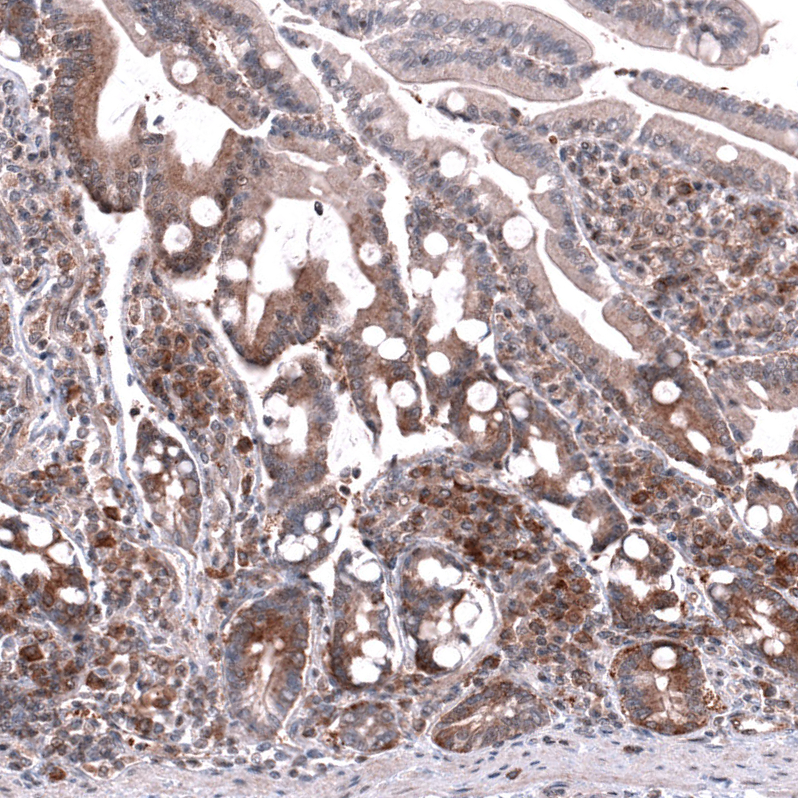

Immunohistochemical staining of human breast cancer shows strong cytoplasmic positivity in tumor cells.